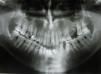

Case reportJ.L.O., a 38-year-old patient was referred to treatment experiencing an extensive lesion involving anterior portion of lower alveolar border with a 10-year progress history. Upon extraoral examination, patient's difficult labial sealing was noticeable by virtue of change in the lower third of the face due to intraoral growth of the lesion. Intraoral clinical evaluation revealed a large-sized lesion involving the anterior portion of the mandible, promoting displacement of teeth 41, 31, 32, 33 and 34 (Fig. 1). Similarly, dental displacement was radiographically clear and the lesion presented slight radiopacity (Fig. 2). Despite the lesion being covered by intact mucosa of normal color, during planning we chose to perform an incisional biopsy prior to definite surgical treatment, by which diagnosis was of inflammatory fibrous hyperplasia. Surgical Access occurred through a wedge incision surrounding the lesion, associated with intrasulcular incision in involved teeth and tissue displacement was performed with the aid of a Molt separator (Fig. 3). Following complete removal of the lesion, dental extraction of involved teeth was performed since they presented compromise of supporting periodontium (Fig. 4). Tissue was repositioned using 5-0 Polypropylene wire and the piece was sent to histopathological examination. Lesion was microscopically described by the presence of dense fibrous connective tissue with multiple vital bone trabeculae, surrounded by uneven pavimentous epithelium (Fig. 5). The presence of mixed inflammatory infiltrate was also seen. In addition to routine HE staining, immunohistochemistry was performed for actin in smooth muscle tissue, in which positivity to HHF-35 was observed (Fig. 6), thus confirming myofibroblastic characteristic of the lesion. Therefore, the diagnosis of excisional biopsy was peripheral ossifying fibroma. The patient recovered with no incidents and clinical and radiographic 12-month follow-up revealed absence of relapses (Figs. 7 and 8).

Upon radiographic evaluation, in some cases the presence of radiopaque diffuse calcifications is observed in a shadow of soft tissues and rarely there is associated bone destruction.4,9 Regarding radiographic appearance of tooth migration, it is present only in 5% of the cases, thus constituting a very rare finding, as well as radicular resorption.1 In this work, marked dental displacement associated with slight radiopacity of the lesion was radiographically observed; however radicular resorption was not seen.